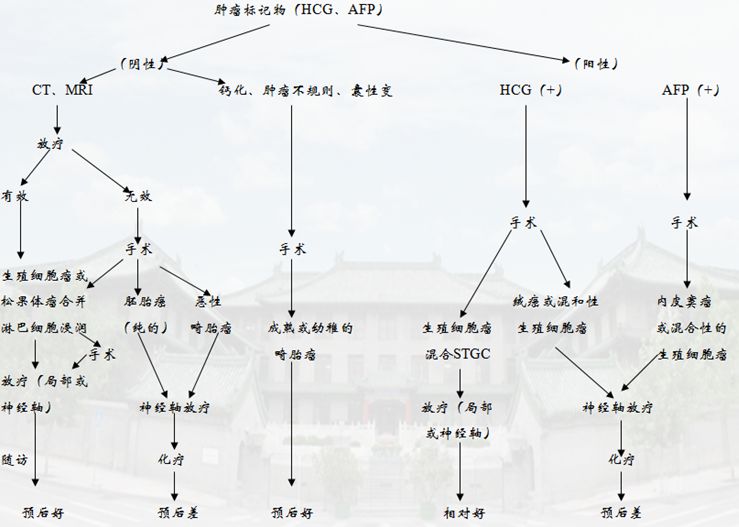

HCG和AFP对诊断的指导:

HCG:肿瘤一定是绒癌或生殖细胞肿瘤合并合胞体滋养层巨细胞成分。绒癌血清HCG>2000mIU/ml;而混合了合胞体滋养层巨细胞成分的生殖细胞瘤血清HCG<1000mIU/ml

AFP:肿瘤一定是内皮窦瘤(卵黄囊肿瘤)或混和了内皮窦瘤成分的生殖细胞瘤。如果AFP和HCG阴性,肿瘤可能是生殖细胞瘤、胚胎癌、成熟的畸胎瘤、幼稚的畸胎瘤、恶性畸胎瘤、生殖细胞瘤混合其它的成分、松果体实质肿瘤(松果体瘤、松果体母细胞瘤、松果体瘤合并淋巴细胞浸润)。纯正的胚胎癌如果不合并内皮窦瘤或绒癌成分,AFP和HCG都可以是阴性的,但是非常罕见。

如果20Gy放疗可以有效的使肿瘤体积缩小,说明肿瘤为生殖细胞瘤或来源于2种细胞成分的松果体瘤合并淋巴细胞浸润。这类病人可以追加放疗到50Gy

但是如果肿瘤直径大于2cm(有时是1.5cm),建议直接切除肿瘤,然后再进行放化疗。